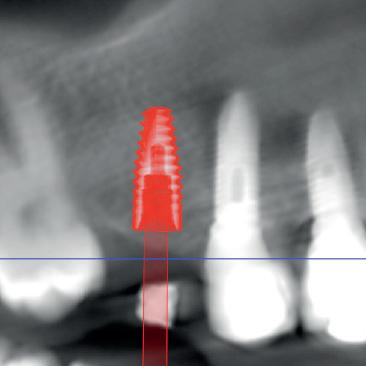

• Combiner les différents examens numériques pour réaliser des plannifications implantaires et prothètiques.

• La plannification implantaire numérique.

• Design de guides chirurgicaux, de prothèse provisoire et définitive.

• Anticiper la position clinique de l’implant à partir de sa position virtuelle.